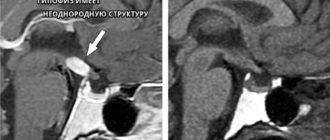

Что такое диффузно-неоднородная структура гипофиза и чем это опасно Гипофиз или питуитарная железа, играет